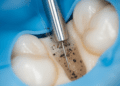

O tratamento visa eliminar a causa da irritação para permitir a recuperação da polpa. As principais condutas são:

- Remoção da cárie: Uma cavidade deve ser cuidadosamente preparada para remover tecido cariado;

- Restauração adequada: Uso de materiais que proporcionem vedação e proteção da polpa, como resinas compostas;

Em alguns casos, pode ser necessária a aplicação de medicamentos específicos na cavidade para promover a cicatrização pulpar, como o hidróxido de cálcio. Se o tratamento for realizado adequadamente, a polpite reversível geralmente apresenta excelente prognóstico.